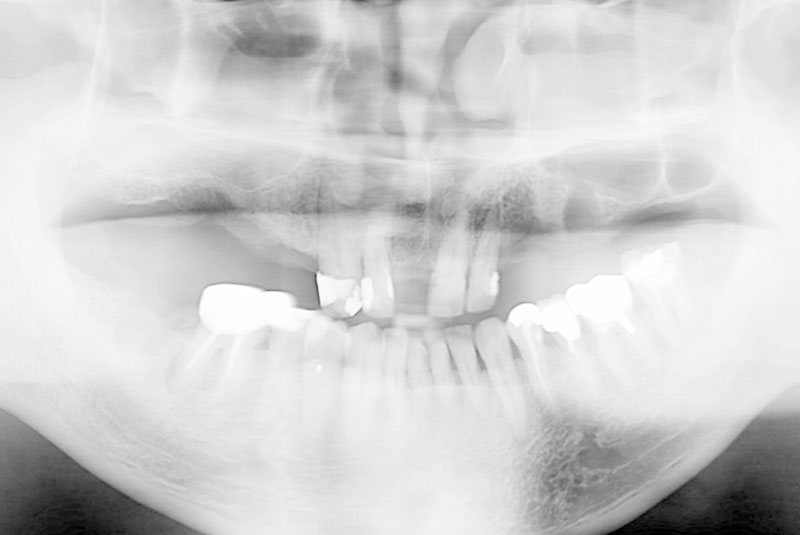

多数歯欠損のインプラント(サイナスリフト・GBR併用)

- 治療経過

- 前医にて上顎部分入れ歯を装着、下顎の奥歯を抜歯した状態で来院されました。また下顎の両側の臼歯の抜歯が必要と診断されたとのことでした。前医にインプラントを相談したが下顎はできるが、上顎は骨がないことを理由にインプラント不可能と診断され当院受診されました。診断の結果、下顎臼歯は保存可能、上顎臼歯部は左右上顎洞に対する骨造成(サイナスリフト)、前歯部はGBRにて骨造成を行い、インプラント埋入を行いました。

サイナスリフトはかなり専門性の高い外科処置であるため対応できる歯科医師は限られます。そのためショートインプラントや傾斜埋入で対応されることも多いですが、患者さんの年齢や希望を伺いながら当院では必要であれば積極的に行っております。その他不良補綴物の除去、根管治療、虫歯治療を行い全顎に対して審美的修復を行い治療終了までに2年を要しました。ちなみに当院では1本も抜歯は行いませんでした。保存できる歯と抜歯の必要な歯をしっかり診断することも必要です。